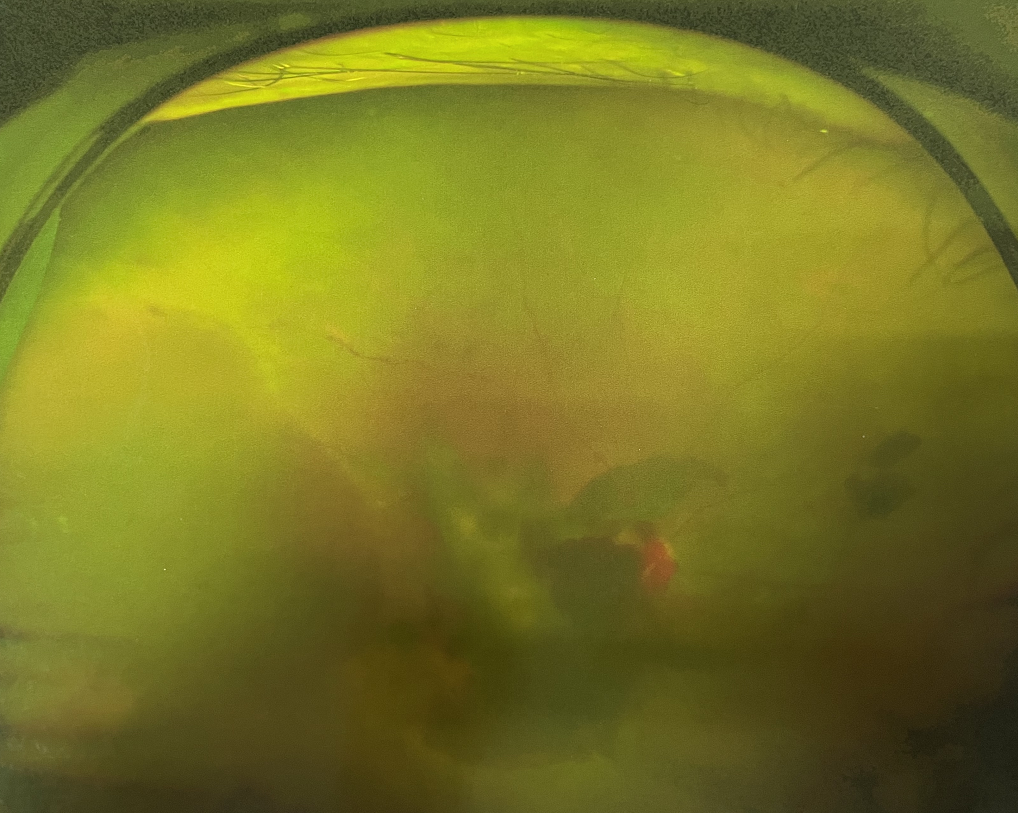

【文章導(dǎo)讀】糖尿病視網(wǎng)膜病變是糖尿病在眼部的主要并發(fā)癥,是我國四大致盲眼病之一,主要以視網(wǎng)膜血管改變?yōu)椴±硖卣?。眼底多表現(xiàn)為視網(wǎng)膜出血、滲出、新生血管及增殖膜形成,嚴(yán)重威脅患者

糖尿病視網(wǎng)膜病變是糖尿病在眼部的主要并發(fā)癥,是我國四大致盲眼病之一,主要以視網(wǎng)膜血管改變?yōu)椴±硖卣?。眼底多表現(xiàn)為視網(wǎng)膜出血、滲出、新生血管及增殖膜形成,嚴(yán)重威脅患者的視覺健康。

糖尿病視網(wǎng)膜病變

糖尿病視網(wǎng)膜病變可分為六期:

?、衿冢河形⒀芰龌虿⒂行〕鲅c(diǎn)。

?、蚱冢河悬S白色“硬性滲出”或并有出血斑。

?、笃冢河邪咨?ldquo;軟性滲出”或并有出血斑。

?、羝冢貉鄣子行律芑虿⒂胁Aw積血。

?、跗冢貉鄣子行律芑虿⒂欣w維膜增生。

?、銎冢貉鄣子行律芑虿⒂欣w維膜增生,并發(fā)視網(wǎng)膜脫離。